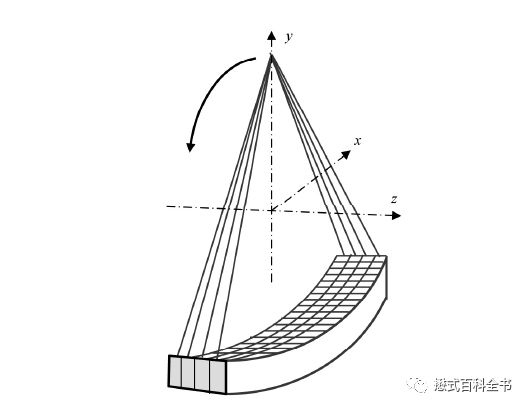

“排”是指CT探测器在Z轴方向的物理排列数目,简单来讲就是有多少排(个)探测器,就是多少排CT,这个指标主要是反映CT硬件结构。可以说排是一个硬件性参数。所谓硬件性参数就是直接可以在硬件(实体)中反映出来的,比如64排,那么可以数出来探测器的阵列数。目前的CT都是多排CT(MDCT),即Multi-detector CT或者可以写成Multi-row CT或者Multiple detector row CT。

前面讲了“排”代表探测器的阵列数,一般来说排越多,探测器宽度越宽,一次扫描完成的宽度越大,一次扫描得到的图像也越多。但是由于探测器的物理排布,组合方式及设计理念的不同,“排”数相同的CT得到的“层”数可能并不一样。

第二次飞越是由单层螺旋CT发展为多层螺旋CT。多层螺旋CT是指在单层螺旋CT的基础上,增加了探测器在Z轴方向上的-排列数目,这样可以使X线管旋转一周,完成多个层面(断面)的数据采集。相比于单层CT,多层螺旋CT的主要优势在于扫描速度的大幅度提高。扫描速度提高以后,我们可以做很多新的项目,如一些呼吸运动器官的扫描得以实现。另外,由于Z轴(即层面方向)的探测器数目增加,使CT扫描的层厚得以更薄,提高了Z轴方向的空间分辨率或者层间分辨率,这样可以使各项同性成像成为可能。

图11: 4排CT(注意Z轴方向探测器数目)

图12:多排探测器